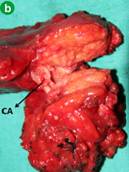

Histopathological examination of the surgical specimen revealed that all surgical margins were free of disease with a tumor of almost 3 cm (Figure 3). The specimen showed a near complete response to neoadjuvant treatment (tumor regression rate 1 calculated with the Ryan score).

Figure 3. Specimen. a. Distal pancreatectomy with spleen. b. The bifurcation of the celiac axis and splenic artery incased with the tumor. CA: celiac axis; SA: splenic artery |

According to the UICC/AJCC staging system the patient had a pT4N1 poorly differentiated adenocarcinoma with two regional metastatic lymph nodes (2/26) and perineural infiltration extending to the celiac plexus.